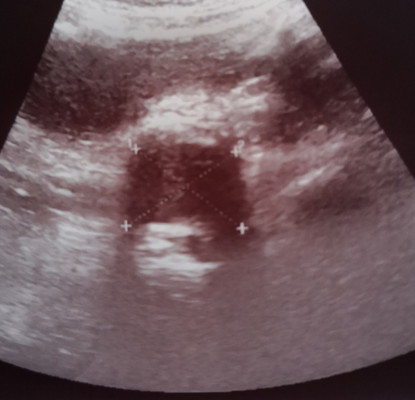

Saya mengandung anak no 2 dalam 14 minggu dan saya mempunyai pregnancy cysts yang size bermula dari 3.4 membesar ke 4.4cm.. Semalam pergi kk scan dan 2 org Dr nampak ada benda putih bawah cysts tapi x tahu apakah benda putih tu Dan suruh refer to pakar.. Appointment dgn pakar belum dapat lagi.. I sangat risau dengan cysts yang membesar Dan benda putih tu...i sangat down....